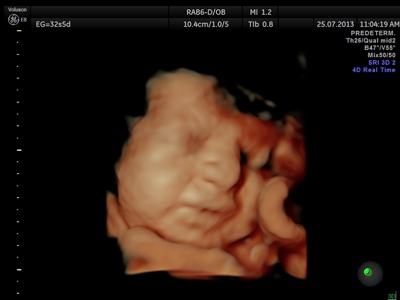

La ecografía 4D HD/5D consiste en la adquisición y presentación continúa de volúmenes. La denominación de la técnica obedece a que hay cuatro dimensiones involucradas: ancho, largo, profundidad y tiempo.

Si bien la Ecografía 4D HD/5D puede realizarse en cualquier etapa del embarazo, recomendamos realizarla entre las semanas 24 a 32 de gestación ya que se pueden observar rasgos bien definidos en el bebe.

Fotografías de ecografías 4D HD/5D

Haga click sobre las imágenes para ampliar